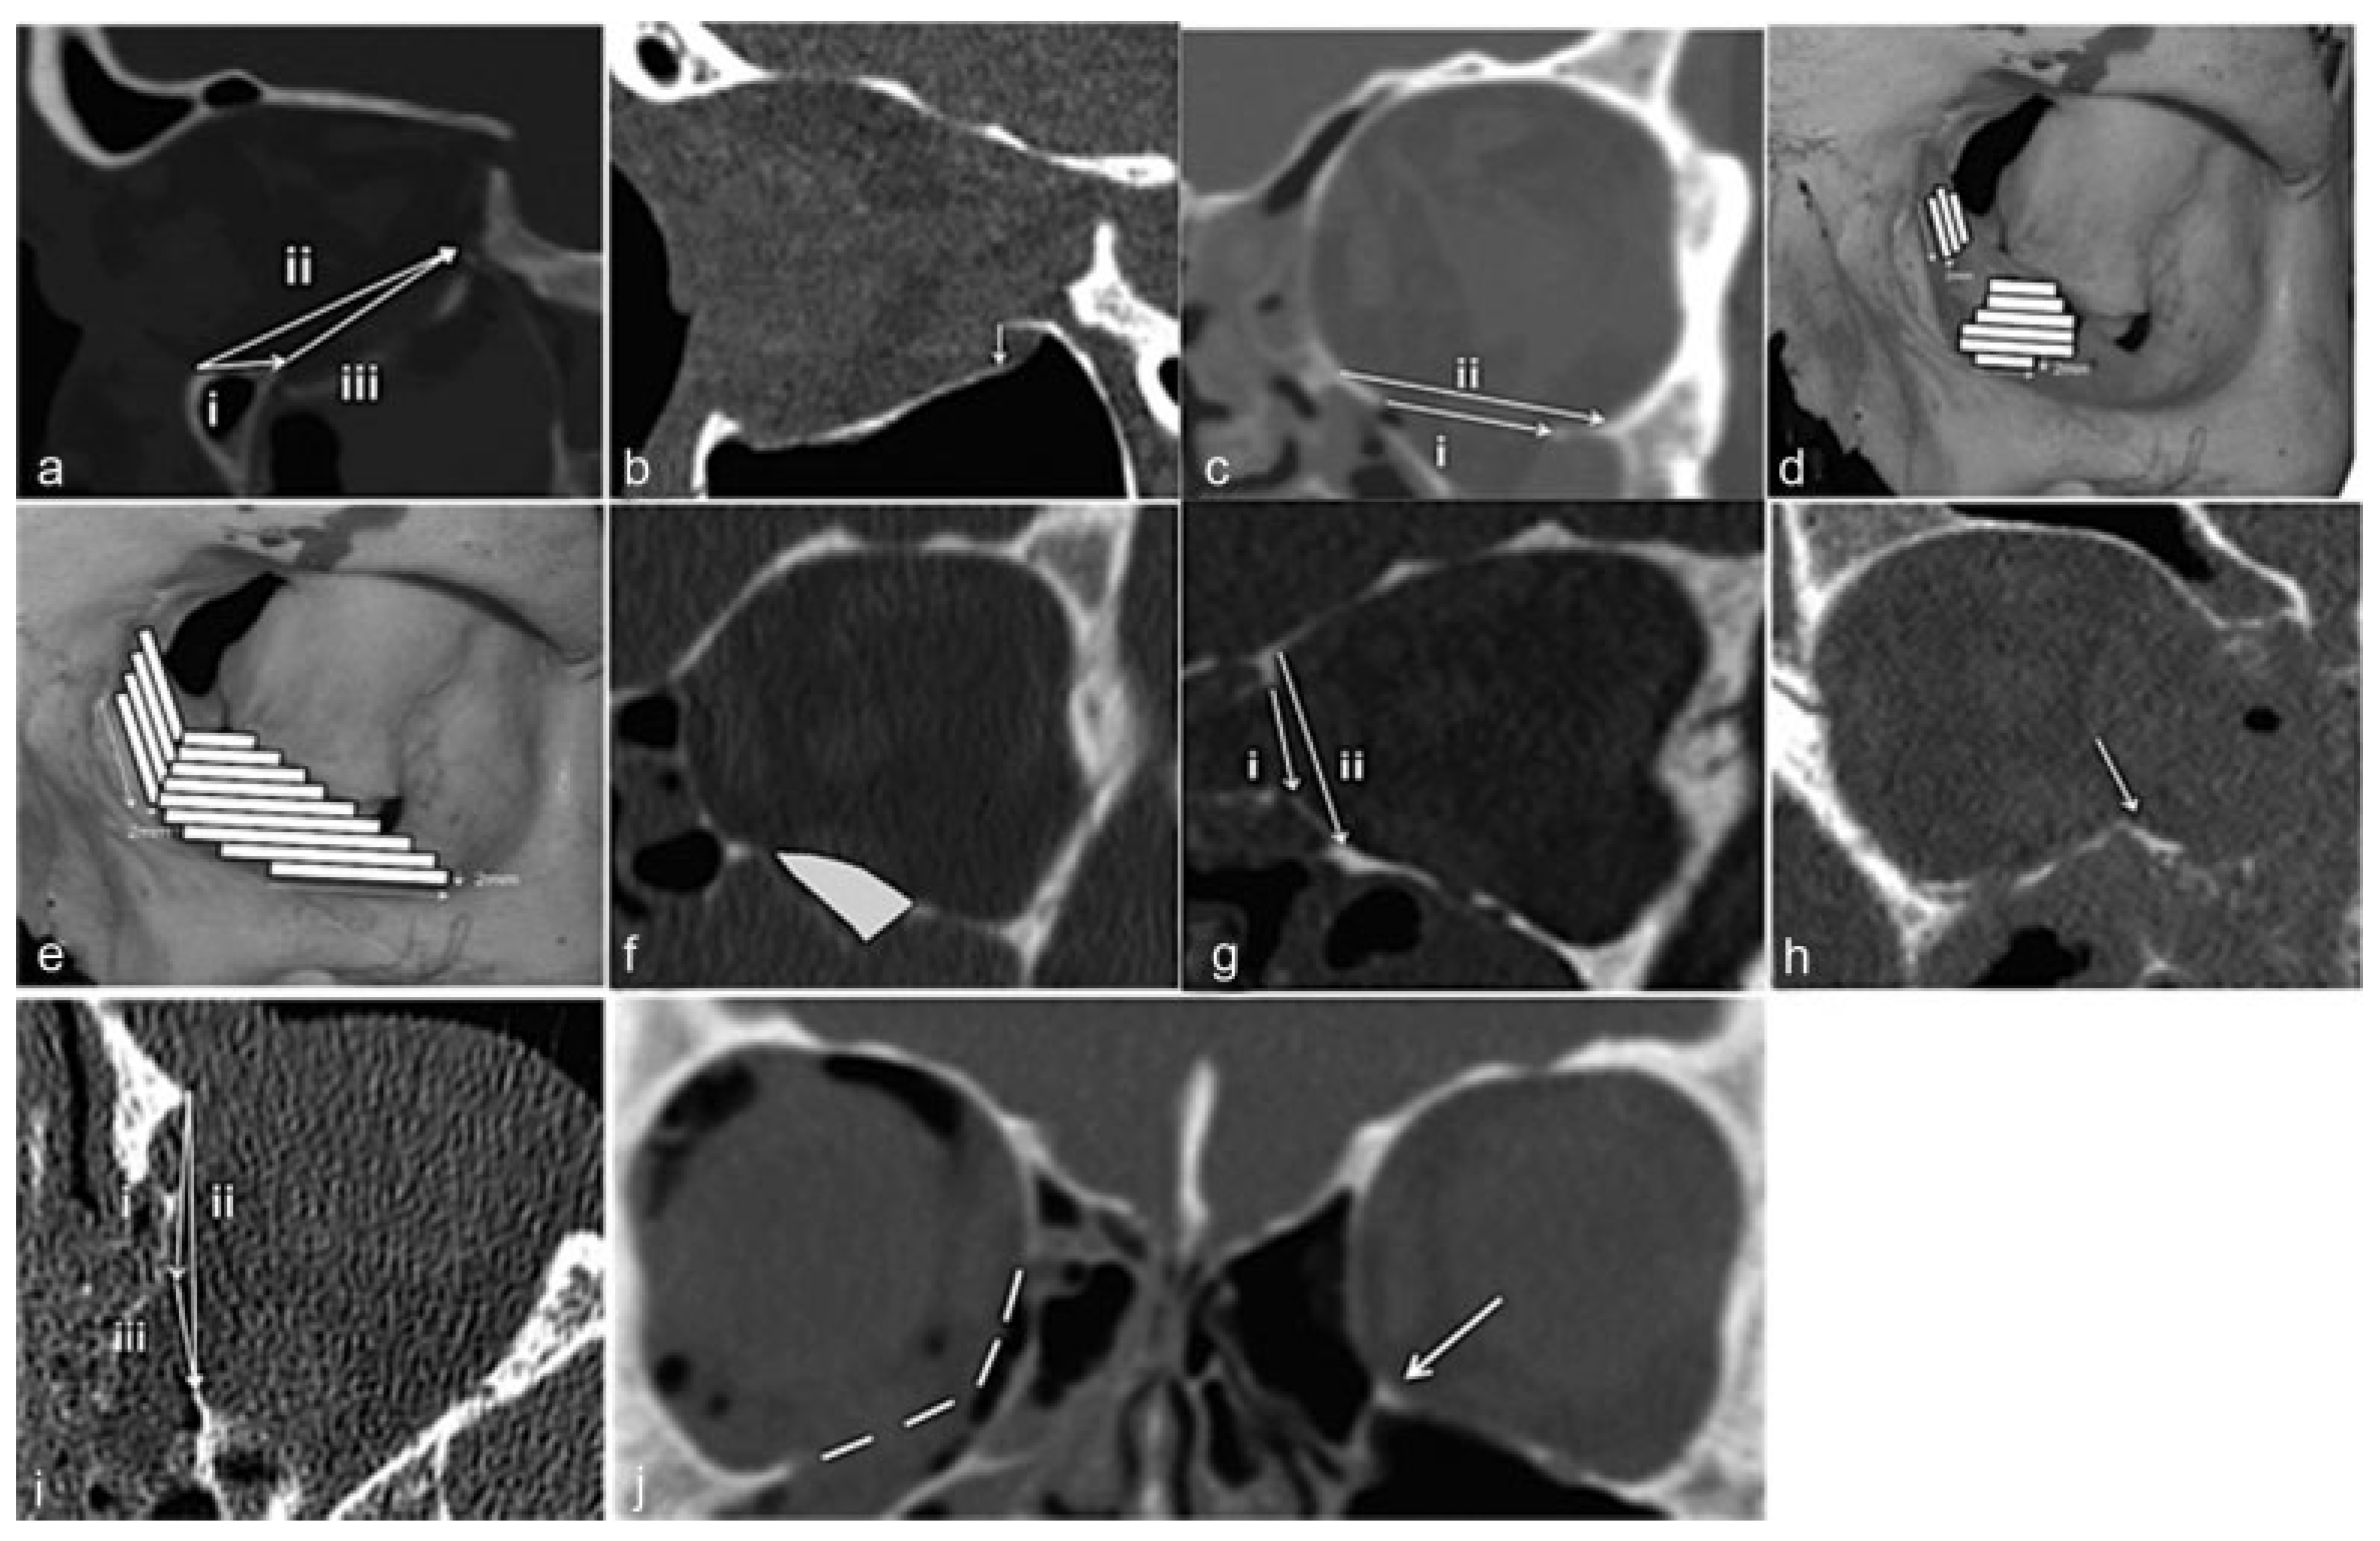

Measurements were made as per the following:

Sagittal plane where the fracture was considered largest in the inferior wall.

• The distance from the inferior orbital rim to the anterior edge of the fracture (Figure 2a, i), on the same slice.

• The distance from the inferior orbital rim to the posterior edge of the fracture (Figure 2a, ii), on the same slice.

• The longest anteroposterior length of the fracture (Figure 2a, iii).

• The largest degree of displacement of orbital bulge in mm (Figure 2b).

Coronal plane:

• The largest width of the fracture (Figure 2c, i) and the wall (Figure 2C, ii).

• The ratio between the largest width of the fracture and the total width of the fractured orbital wall on the same slice.

• The area of the fracture (Figure 2d), respectively.

• The total area of fractured orbital wall (Figure 2e), respectively.

• The ratio between fracture and the fractured orbital wall areas.

• The volume of the herniated orbital tissue (Figure 2f).

• In medial wall fractures, the superoinferior extent of the fracture was measured as the width of the fracture (Figure 2g, i) and on the same slice the superoinferior extent of the total wall (Figure 2g, ii).

• If the inferomedial buttress was fractured and dislocated (Figure 2h).

• In axial plane where the fracture was considered as largest in the medial wall: the distance from the anterior lacrimal crest to the anterior edge of the fracture (Figure 2i, i), on the same slice.

• The distance from the anterior lacrimal crest to the posterior edge of the fracture (Figure 2i, ii), on the same slice.

• The longest anteroposterior length of the fracture (Figure 2i, iii).

Figure 2. (a) Inferior orbital rim to anterior edge of the fx i, posterior edge of the fx ii and the longest anteroposterior length of the fx iii. (b) Displacement of orbital bulge. (c) Largest width of the fx i and the orbital floor ii. (d) Area of the fx. (e) Area of the fractured orbital wall. (f) Volume of the herniated orbital tissue. (g) Superoinferior extent of the fx i and superoinferior extent of the wall ii. (h) Medial buttress fractured and dislocated. (i) Anterior lacrimal crest to anterior edge of the fracture i, posterior edge of the fracture ii and longest anteroposterior length of the fx iii. (j) Estimation of displaced inferomedial buttress in comparison with the unfractured contralateral orbit and inferomedial buttress (arrow). fx, fracture.